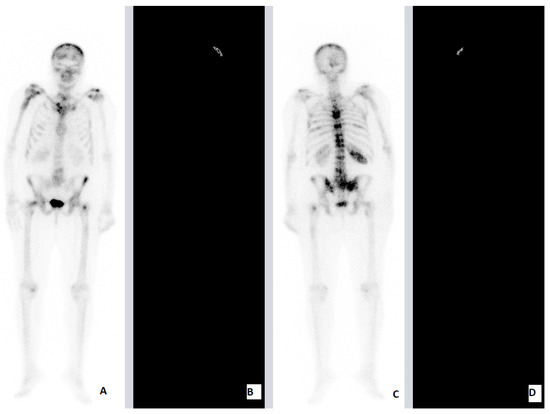

| PCa | 83 | M | HFRT | 20 Gy (4 Gy) | Lhs SJ Stn Lhs Fmr | Lhs SJ | ADT | Concomitant | Stn Lhs Fmr | 1.5 | 4 |

| PCa | 75 | M | HFRT | 20 Gy (4 Gy) | 5th, 6th, 7th, 8th TV 2nd Rhs Rib Rhs SJ | 5th, 6th, 7th, 8th TV | ADT | Concomitant | 2nd Rhs Rib Rhs Fmr | 1.5 | 4 |